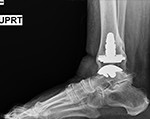

Ankle Joint replacement has dramatically improved the treatment of ankle arthritis over the past decade leading to decreased pain and an improvement in function.

The development of patient-specific technology has further enhanced the accuracy of implant alignment and decreased the surgical time.

Antibiotics are given and the Ankle Joint replacement procedure is performed at Houston Methodist Sugar Land Hospital in the sterile operating room environment.